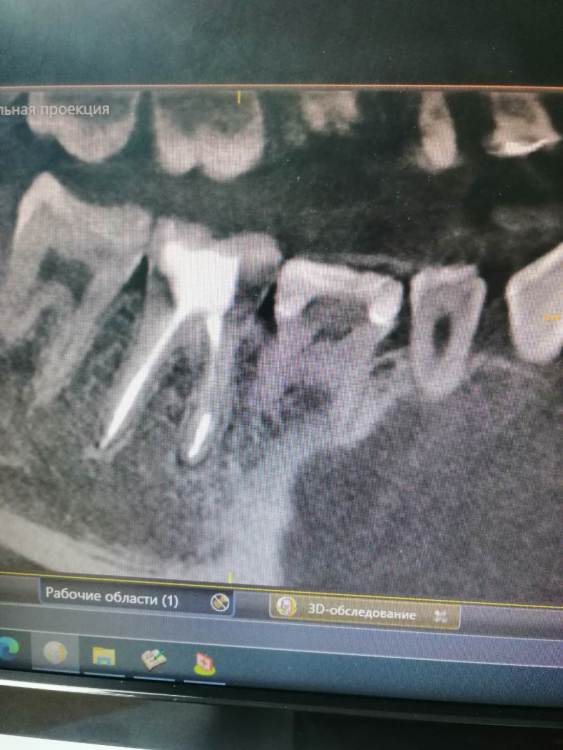

Тильда Опубликовано 30 апреля, 2021 Поделиться Опубликовано 30 апреля, 2021 (изменено) Коллеги, очень нужен ваш совет. В октябре 2020 года проведено эндо лечение 4.6 по диагноз пульпит хронический. Лечение было проведено в одно посещение, ирригант - гипохлорит, M-Two до 30 медиальные и до 40 дистальный, вертикальная конденсация. Недавно (через пол года после лечения) пациентка обратилась снова с жалобами на боли в области пролеченного ранее зуба. Причём причинный зуб локализует чётко. Боли появились сразу после лечения, постепенно немного стихли, но полностью не болит. Болит при механическом раздражение вестибулярной стенки, по словам пациентки отдаёт по челюсти. Перкуссия и термо проба безболезеннные. Слизистая без особенностей. На одном из срезов КТ можно заподозрить расширение периодонтальной щели в периапикальной области медиальных корне, но вроде бы и до лечения картина похожая. Есть ли смысл сделать повторное эндо? Буду благодарна за ваши мысли по поводу дальнейшей тактики. Извиняюсь за качество снимков и понимаю, что их сложно оценить Изменено 30 апреля, 2021 пользователем Тильда Ссылка на комментарий